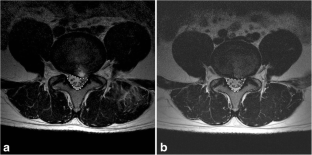

Fig. 1